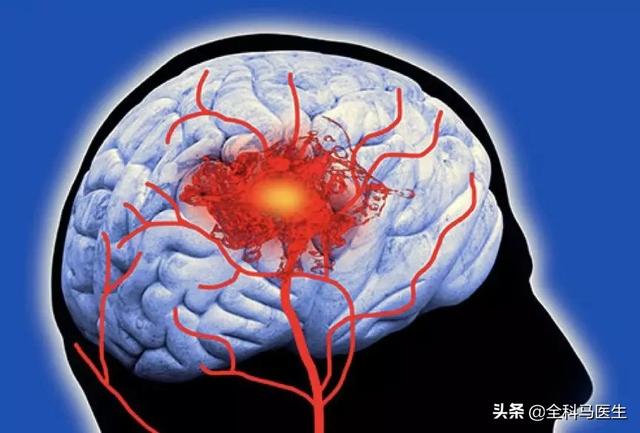

第6 脳血管障害によるもの

特に高齢者では、片腕のしびれや手指のしびれ、手足の脱力を伴う場合には、脳血管障害の発生に注意する必要がある。

4.脳血管疾患

脳血管障害の前駆症状であれ、すでに発症した後の症状であれ、脳血管障害のリスクが高い人にとって、指のしびれは特に注意すべき症状の一つであると言える。ただし、脳血管障害による手指のしびれは、他の症状を伴うことが多く、単独の症状として手指のしびれがみられることもまれではないことを指摘しておく。

まず、脳血管疾患は、指のしびれが原因の脳血管疾患に対して、虚血性脳血管疾患であれば、患者に血行を改善させるだけでなく、栄養神経治療を行うことができ、一般的に患者にイチョウ葉製剤やメチルコバラミン製剤を与えることができます。脳血管障害の急性期であれば、鍼灸治療や漢方薬のイオン導入療法を行うこともできます。

主な問題は、小さな脳梗塞、腫瘍の圧迫、頭蓋内血管奇形の圧迫などである。

一過性脳虚血は手指のしびれの原因として高齢者に多く、特に片側の手足のしびれがある場合に注意が必要である。一過性脳虚血の原因と病態は、脳動脈壁の微小塞栓、脳動脈狭窄に基づく血圧低下、脳血管攣縮などである。上記のような症状が出現した場合には、時間内に病院を受診し、高血圧、高脂血症、高血糖、心房細動などの脳血管障害の危険因子を総合的にスクリーニングし、積極的な予防と治療を行う必要がある。

6.脳梗塞

この病気は、現在、中高年に比較的多い病気で、上肢や手指のしびれが出現することもあり、その原因は、頸動脈圧迫、動脈硬化、脳血栓症などが原因で、脳組織が虚血・低酸素状態になるため、脳神経が障害され、上肢を支配する神経に異常が出現し、それにつながる。